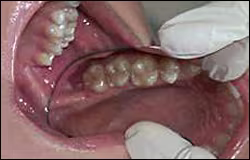

Vault – relates to the depth and width of the palate (Figure 29)

Figure 29. Normal structures of the posterior hard palate.

Observe the dimensions (height and width) of the vault.

Maxillary tuberosities – area distal to the last molars (Figure 30), the tissue should be a homogenous pink color and firm to palpation

Figure 30. Normal maxillary tuberosity.